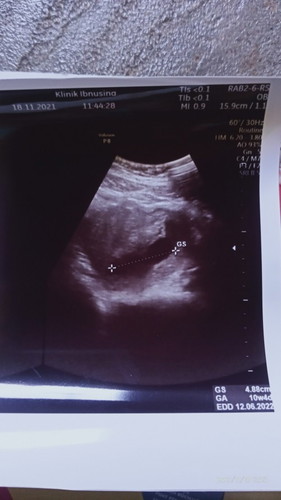

Bunda saya ingin bertanya kehamilan 10minggu usg masih kantongnya aja janinnya belum ada normal kah

maaf bangett bund. itu ga normal bunda.. harusnya udah ada janin dan djj, krn umumnya janin+djj itu ada sekitar 6-8weeks, dan maksimal 9weeks. 10 weeks biasanya dah agak gde dkit bund... coba d tunggu 1 minggu lagi, lalu usg lagi.. kalo sampe 11 weeks blm ada janin dan djj coba d diskusikan sm dokter dan suami gmn baiknya ,krn tindakan dan pemantauan itu maksimal di bawah/sebelum 12 weeks bund secara keilmuan, kalo ada yg suruh usg transvaginal, jgn mau bund, krn usg transvaginal maks 8 weeks atau 8weeks lebih brp hari gtu bund. masuk 9weeks udah ga boleh usg transvaginal ketentuan di ilmu kedokteran, dan harus usg yg perut kalo dah 9 weeks, apalagi ini dah 10 weeks harusnya usg perut sudah terlihat. krn saya dulu 8weeks udah terlihat dg usg perut dan djj udah terdengar(skg udah 21 weeks 4hari) .. sehat2 ya bund. jgn lupa doa.. lebih legowo dan ikhlas, saling menguatkan bersama suami. semoga ada keajaiban.. 1 mnggu lg balik ke dokter ya bund.. bukan gmn2 biar ngerti harus gmn.. peluk jauh bunda π€